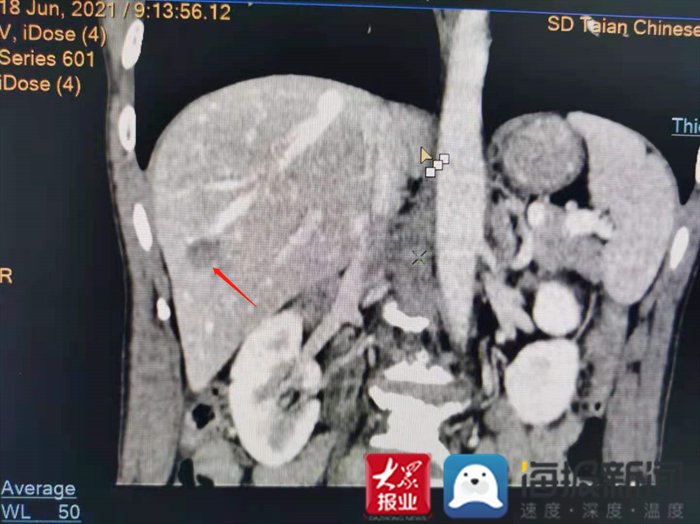

CT显示患者肝右叶S6段见一斑片状低密度灶(红色箭头所示)